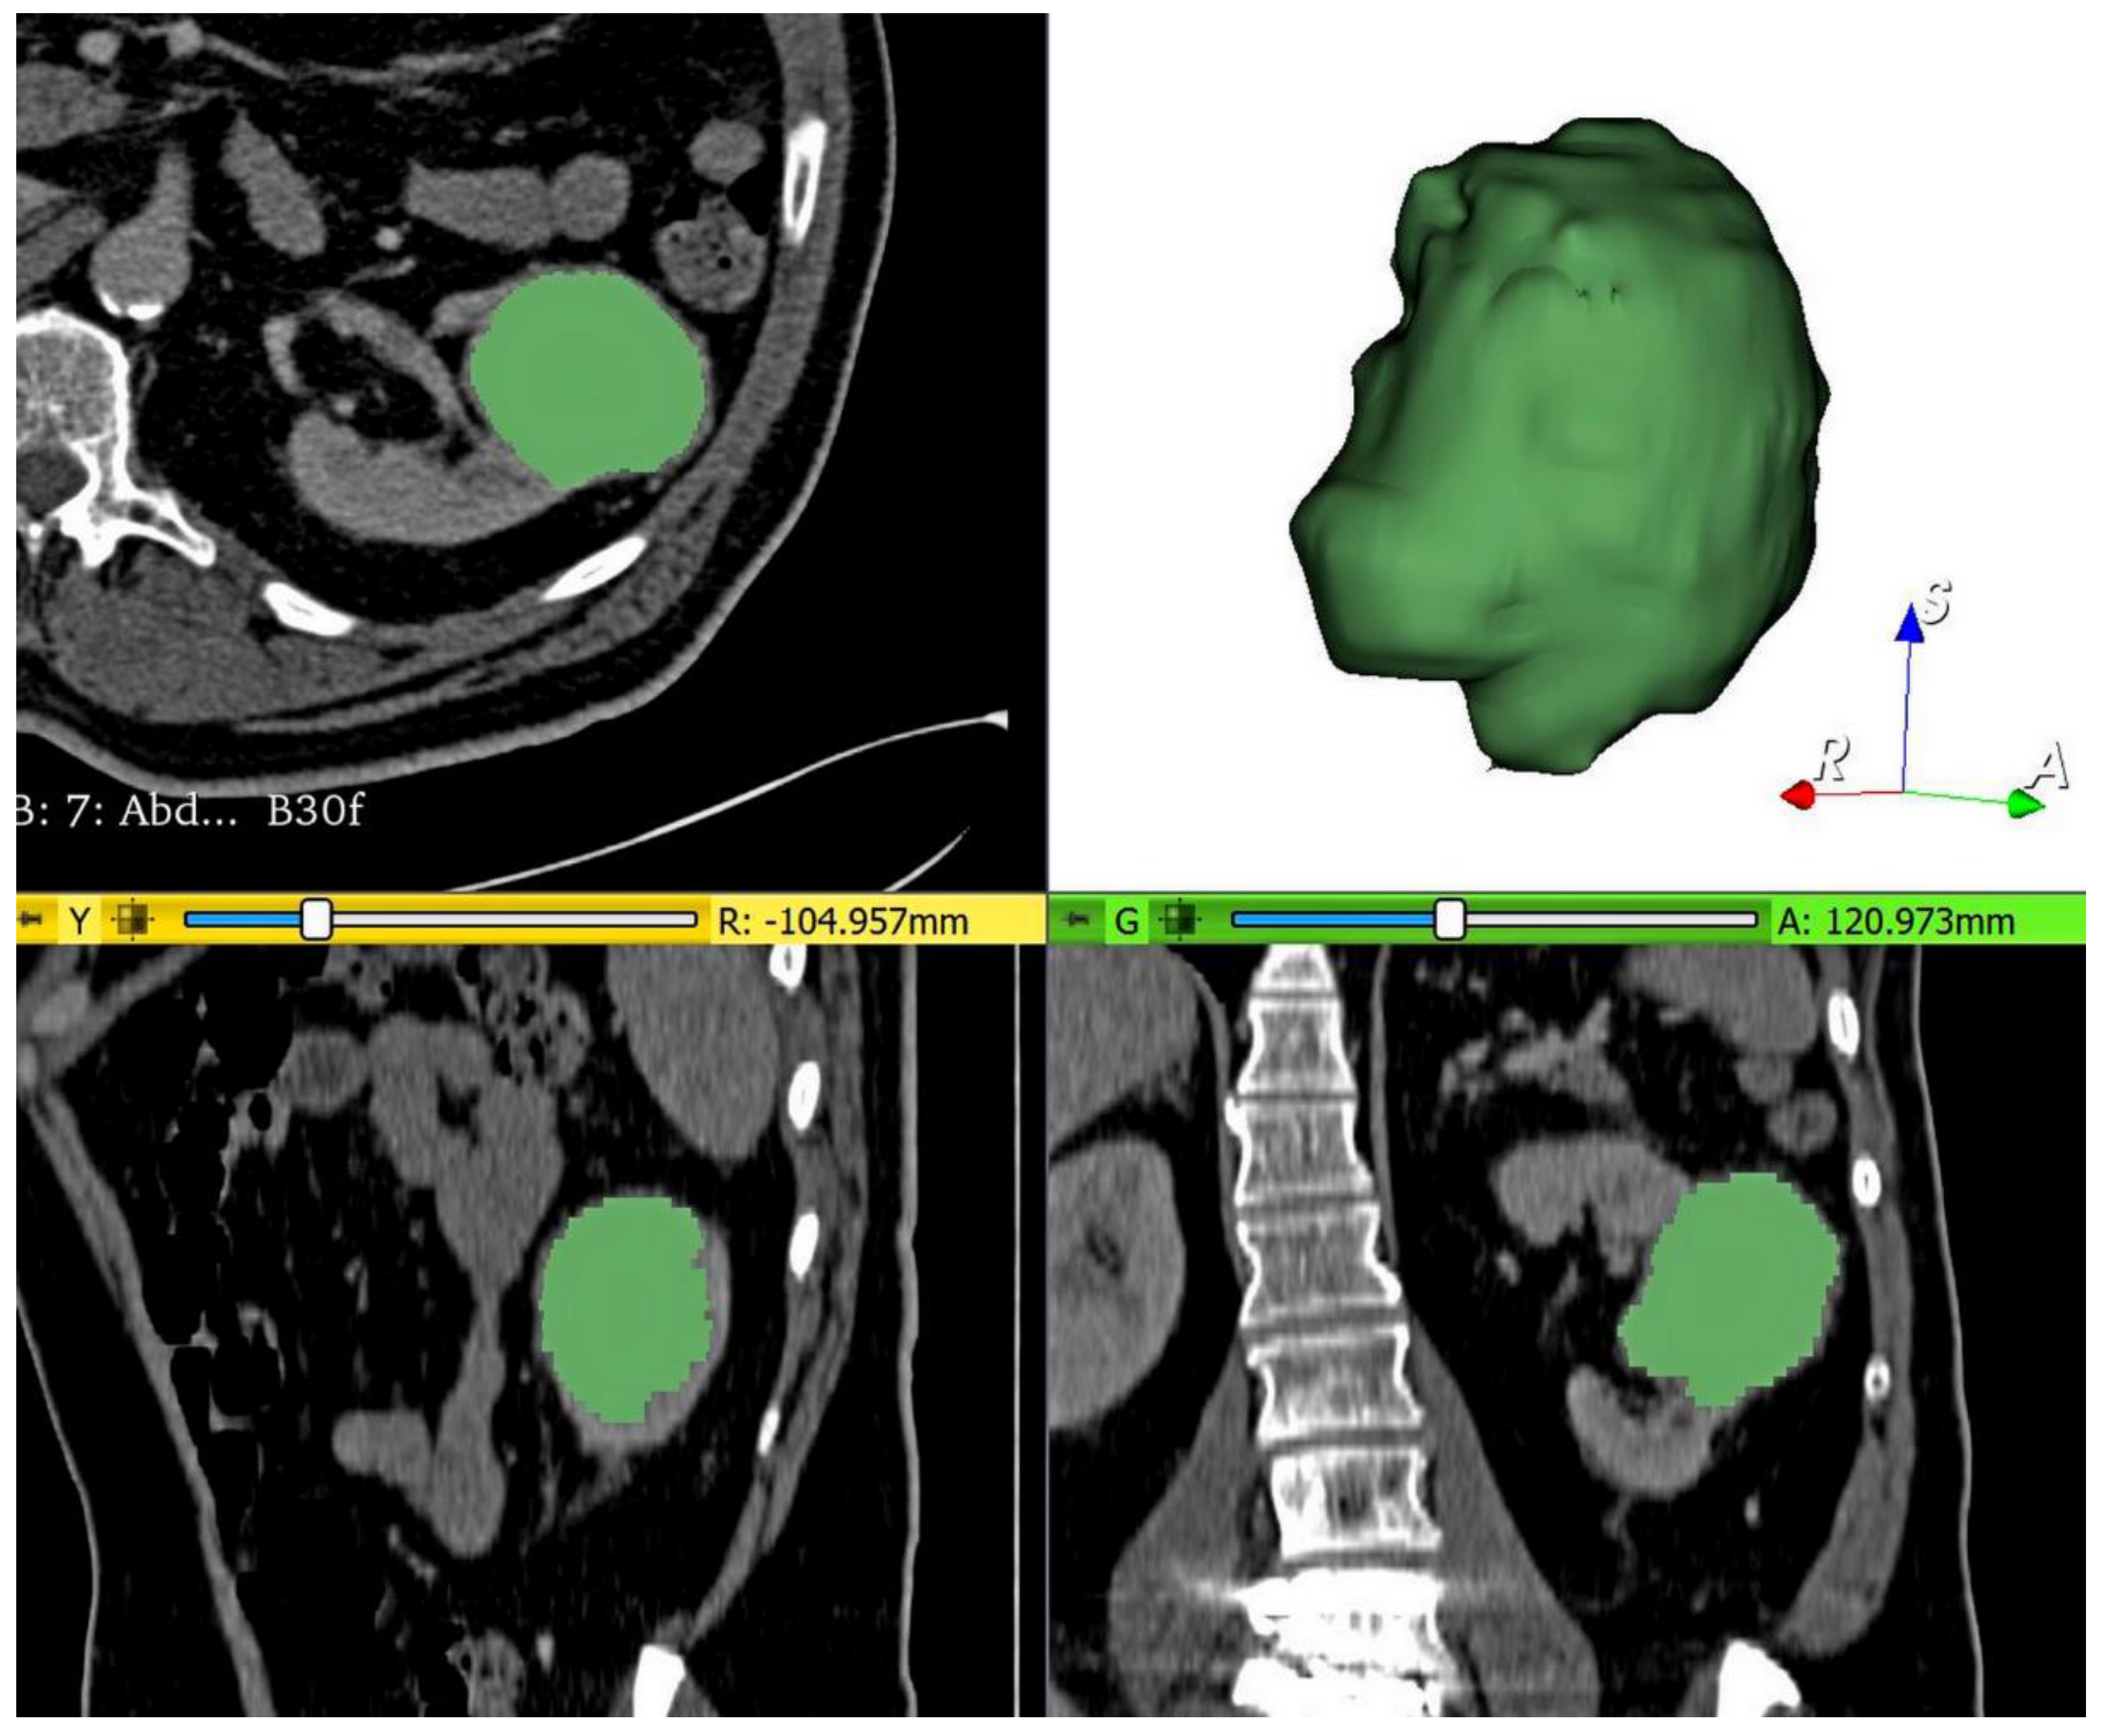

2.4. Tumor Segmentation, Preprocessing, and Radiomics Feature Extraction